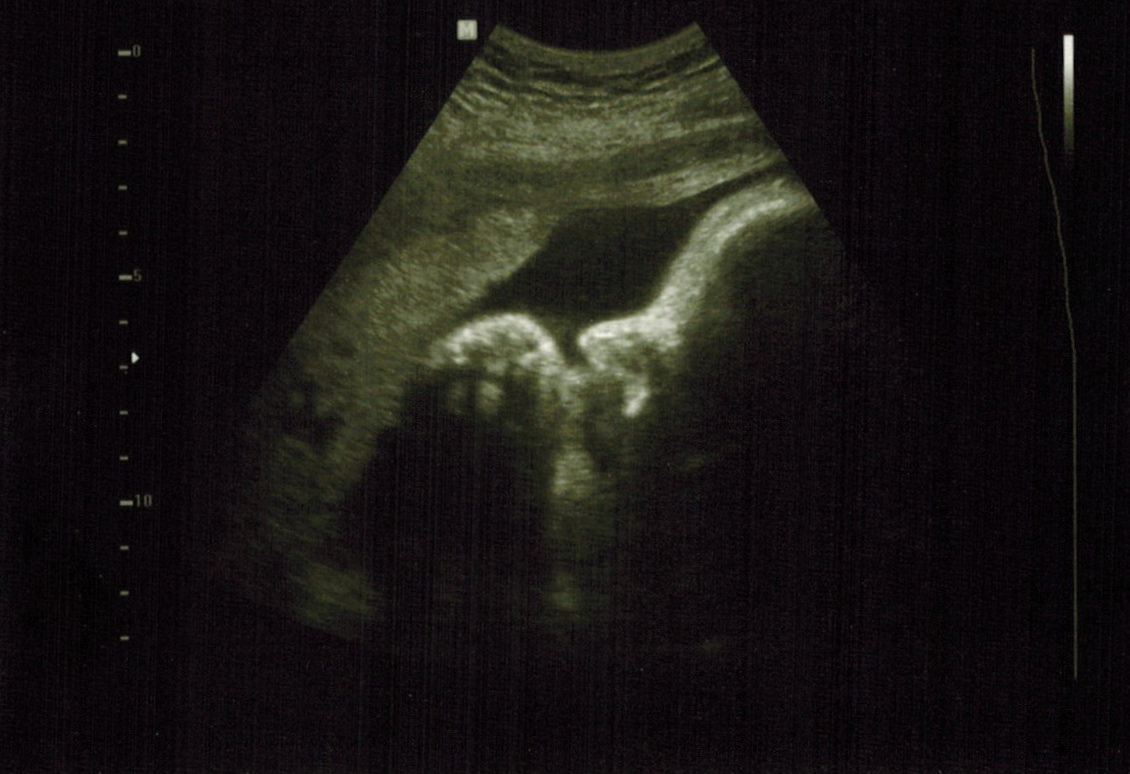

Not too long ago we heard that the local community college has a class that teaches students to do ultrasounds, and they were looking for pregnant women to volunteer to come in so the students could practice on them.

I turned down an extra ultrasound earlier in the pregnancy, but decided to take advantage of this one for two reasons: it was free, and Mr M could attend. He missed the other ultrasounds, so it was nice for him  to still see one.

Since I'm so close to my due date the little guy was a little cramped, but we were able to see some pretty cool stuff. Like we could actually see the vernix floating in the amniotic fluid and the fuzz that is his hair.

At the end the instructor did a few 3-d ultrasounds, and we got a couple good pics.

standard ultrasound, profile of head with hand up to face.

he may have been sucking his thumb, we weren't sure.

3-d ultrasound, head with hands curled up by his face.

look at those chubby cheeks and tiny fingers!

One of them is just a bit creep/disturbing, though. She caught one picture that shows his eye open, and it looks like he's looking straight at us. Just a bit unsettling. The instructor actually kept a copy of this one because she'd never caught an ultrasound with an eye open before.

3-d ultrasound, hands at face again, one eye open and looking at us.

What do you think? Creepy or not?